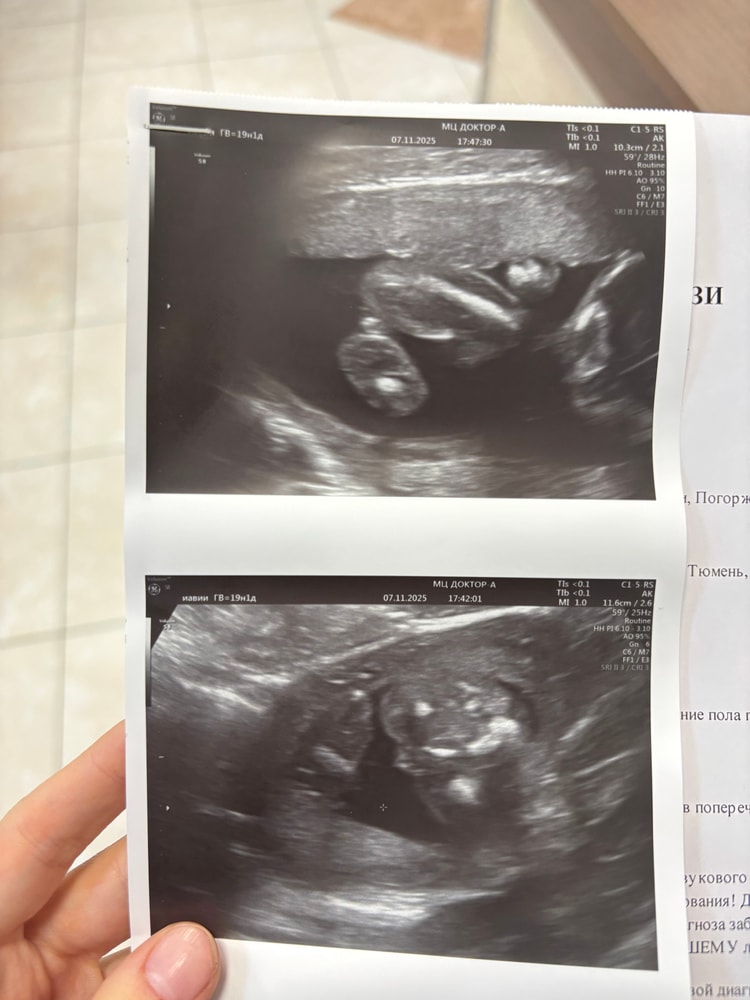

на первом узи в 12 недель врач сказал у вас девочка (но конечно верить не могу на первом узи, так как в 12году с сыном до 3 скрининга говорила девочка, а со вторым в принципе все время говорили мальчик, один раз не поняли кто 😅)

на втором узи в 20 недель врач дал конверт в котором было написан